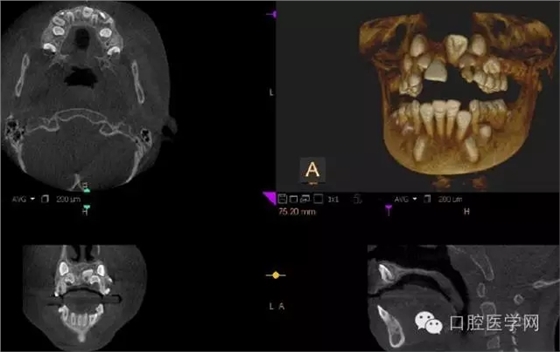

3.牙齒數(shù)目異常

額外牙

X線表現(xiàn):最多見(jiàn)于上頜兩中切牙之間;圓錐形,根短小;拍攝X線片可確定額外牙的數(shù)目、位置、形態(tài)與鄰牙的關(guān)系。

4.阻生牙

最常見(jiàn)于下頜第三磨牙

X線表現(xiàn):確定阻生牙的位置;確定阻生方向;牙根數(shù)目和形態(tài);阻生牙有無(wú)齲齒和根尖情況;與第二磨牙的關(guān)系;與下頜管的距離和磨牙后間隙的大小。